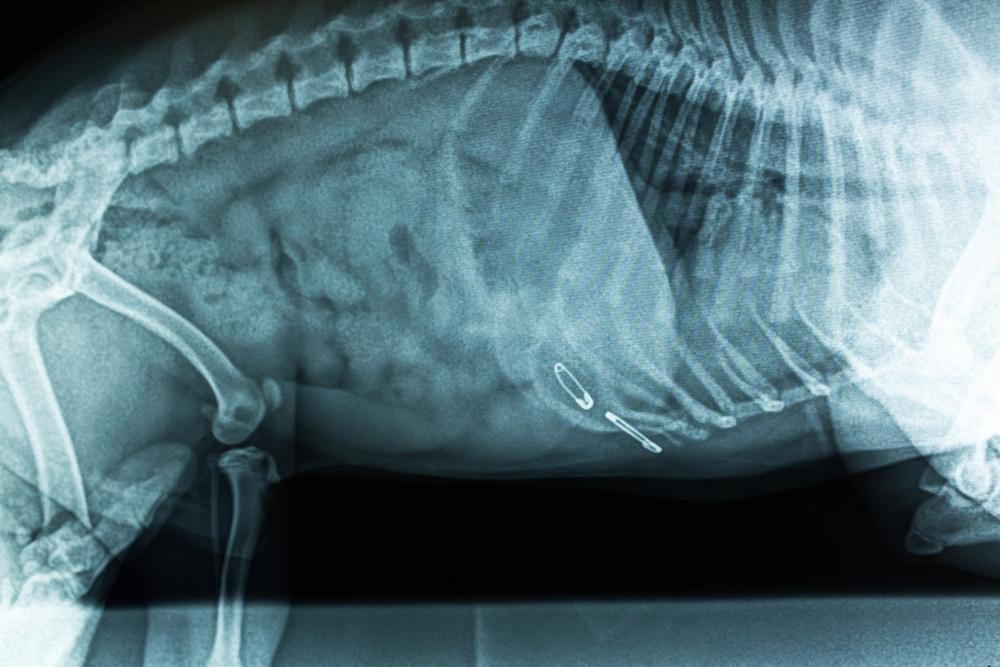

Corpus alienum adalah benda asing yang masuk ke dalam tubuh. Contohnya ketika ada kapas cotton buds yang masuk ke telinga atau staples yang tertelan bersama makanan.

Benda asing bisa masuk ke dalam tubuh melalui berbagai cara, seperti lewat mulut, hidung, hingga lubang telinga. Biasanya, corpal ditemukan di kerongkongan, perut, dan usus.

- Endoskopi: memasukkan alat berbentuk tabung panjang yang lentur untuk mengamati bagian organ dalam tubuh, seperti lambung, usus, laring, dan lain-lain.

- Bronkoskopi: prosedur endoskopi pada saluran pernapasan untuk mengamati bronkus dan paru-paru.

Pembedahan merupakan cara terakhir yang digunakan untuk mengeluarkan benda asing apabila berbagai cara di atas tidak berhasil.